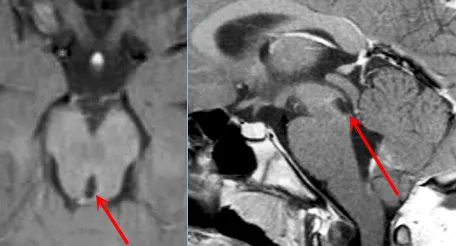

术后影像

几天后,手术如期进行,并在巴教授团队数小时奋战下取得成功,肿瘤被顺利切除。病理显示为WHOⅢ级间变性星形细胞瘤(Anaplastic Astrocytoma)。

如今,在巴教授15年的随访下,马修已经顺利成年,尽管他的童年遭遇过不幸,但一场成功的手术,为他争取到了完整的少年与青年。看着如今笑容满面、意气风发的马修,父母无比庆幸当年的选择没有给孩子造成严重的后果,反而挽救了他。